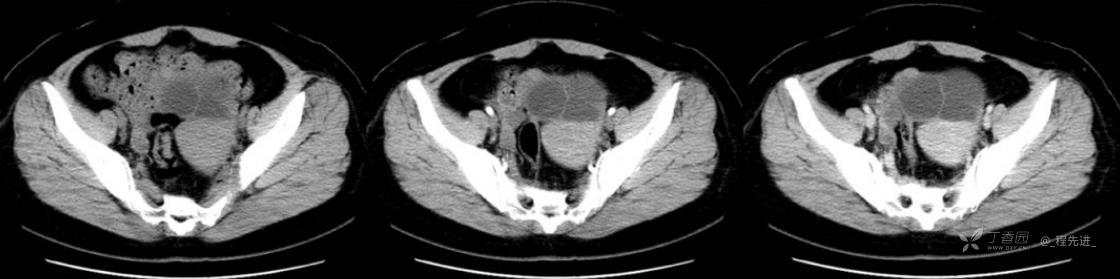

1月特别精彩病例|中老年女性,盆腔包块近半年持续增大【病理已公布】

患者年龄:53岁

简要病史:4年前体检时发现盆腔包块及子宫肌瘤,近半年复查盆腔彩超发现包块持续增大,近1年月经欠规律,伴腰、腹胀。

体格检查:宫颈举痛(+),子宫增大,质地中等,活动可,无压痛;右下腹轻压痛,无反跳痛,左侧附件区未扪及明显包块,无压痛。

阴式彩超:子宫约65*58*44mm大小,子宫肌层可见多个低回声块影,较大的为35*27mm(位于子宫前壁下段偏右侧壁),边界清,内回声欠均匀,后方回声衰减。考虑子宫多发肌瘤。子宫后壁可见一混合回声包块,大小约31*20mm,边界不清,内呈强弱回声,分布不均,考虑子宫腺肌瘤,其他疾患待删。子宫内膜厚6mm,宫颈可见多个囊性暗区,边界清,内透声好,后壁效应增强,较大的为15*11mm。子宫前方偏左侧可探及一大小89*75mm囊性肿块,边界清,壁薄光滑,内透声好,可见分隔光带